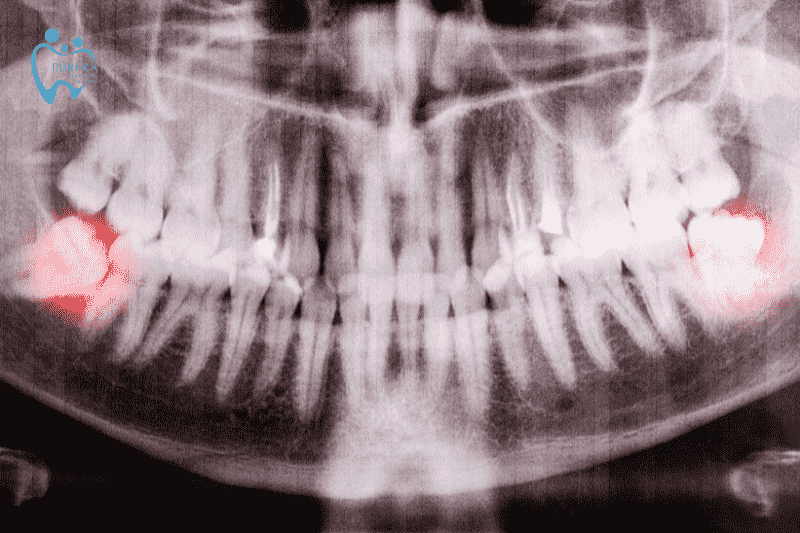

Việc nhổ dự phòng răng khôn hàm dưới mọc lệch, mọc ngầm có thể giúp tránh được những tai biến đau nhức cho người bệnh. Khi nhổ răng khôn cần đi khám chuyên khoa. Bác sĩ sẽ dựa trên phim X-quang để xác định vị trí, chiều thế và phương pháp nhổ thích hợp.

- Vị trí: Nằm phía trong cùng của hai hàm răng, hay còn gọi là răng cối thứ ba. Chúng thường mọc sau răng số 7 và ngay góc hàm

2.2 Một số tình trạng mọc răng khôn phổ biến

- Răng khôn mọc ngang hoặc nghiêng (horizontal impaction): Một số trường hợp đặc biệt răng khôn có thể mọc nghiêng hoặc nằm ngang, không thể mọc thẳng đứng bình thường làm cho nướu đau, tạo áp lực và có khả năng xung huyết trong những vùng xung quanh